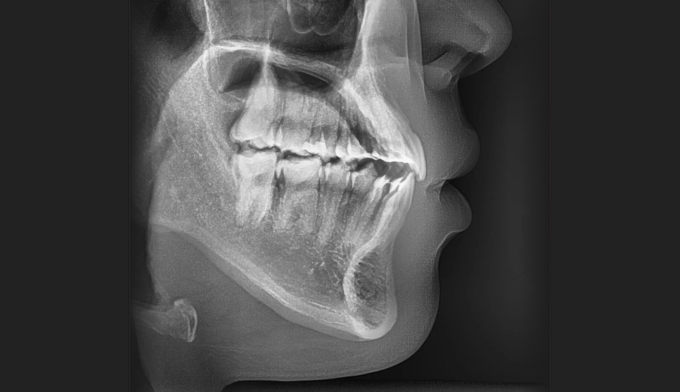

주걱턱 경향을 갖는 청소년들은 개방교합과 덧니를 동시에 갖는 경우가 많습니다. 아래턱의 과도한 성장은 혀의 위치를 아래로 처지게 만들고, 이는 위턱의 폭을 줄어들게 만들어 덧니가 생기기 쉽게 만듭니다. 그리고 과도한 아래턱의 성장은 앞니의 교합을 벌어지게 만들어 개방교합 또한 나타나게 됩니다.

좁아진 위턱 악궁을 확장시켜서 치아를 배열시키고, 과도하게 앞으로 나온 앞니를 미니스크류를 이용하여 후방이동 시킵니다.

총 치료기간은 24개월 소요되었습니다.

남자아이들의 경우에는 성장이 고등학교 이후에도 지속되는 경우가 많으므로 치료 이후에도 주기적으로 성장을 관찰하여야 합니다.